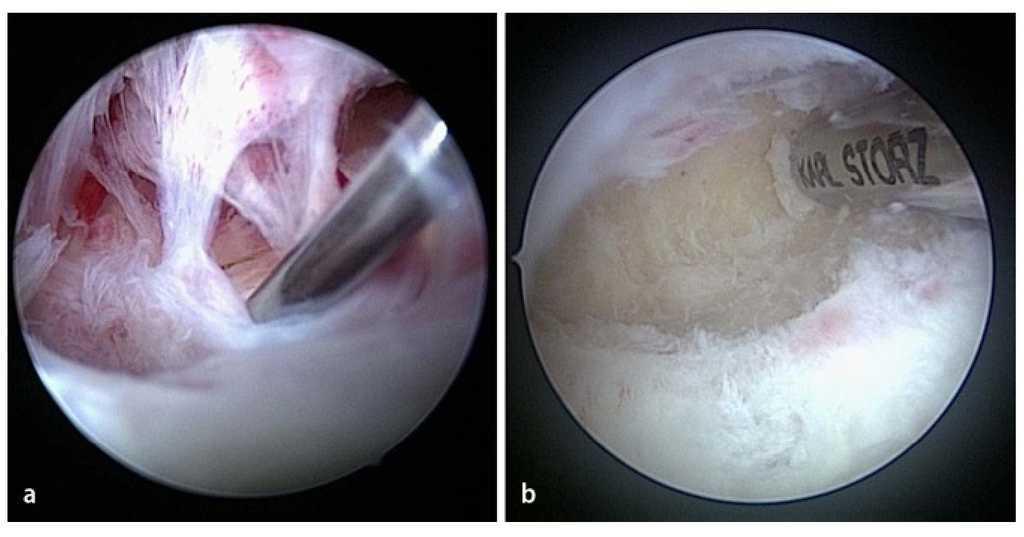

Fig. 13 Para finalizar, se verifica la amplitud de movimiento del codo. En caso de déficit en flexión remanente se puede realizar una liberación capsular en el compartimento anterior bajo control artroscópico. La cápsula se separa con precaución de sus inserciones en el húmero distal mediante el resector sinovial. Como alternativa se puede utilizar también un raspador.

Fig. 14 La artroscopia en el compartimento posterior se inicia con la realización del abordaje dorsorradial y del abordaje transtendinoso desde el cual se introducirán los instrumentos (Figs. 6c). En el ángulo visual de la cámara por encima del portal posteroradial se encuentran la punta del olécranon y la fosa olecraniana. a) Con frecuencia existen adherencias masivas en la zona de la fosa olecraniana, que se separan con un resector sinovial y se extraen. b) En los casos con graves limitaciones de movimiento se puede realizar también una cirugía de la fosa con una fresa para hueso (no se representa en la imagen). Mediante esta cirugía se extraen las formaciones óseas molestas, así como formaciones osteofíticas en la zona de la fosa olecraniana, hasta que se restituye la libre movilidad entre el olécranon y la fosa olecraniana.